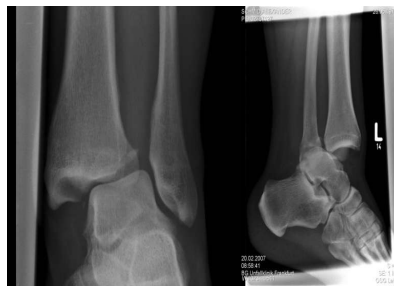

Knochenbruchzeichen

bildgebend:

Röntgenaufnahmen in 2 oder 3 Ebenen

CT,MRT

Durchleuchtung unter Funktion (ggf. unter Narkose)

Epiphysen(Wachtumszonen)fraktuen nach Aitken - körperferne Tibia (Schienbein)

a) Aitken 0

Epiphysen-Lösung

b) Aitken 1

Fraktur am körpernahen Anteil

c) Aitken 2

Fraktur körperferner Anteil

Epiphyse evtl. mit abgebrochen

d) Aitken 3

Fraktur: körpernaher/körperferner Anteil

Beide teile ober/unterhalb Epiphyse ab